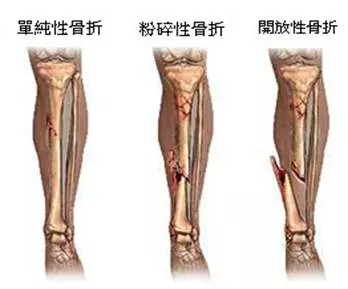

外伤骨头——粗看X线片,细看CT,核磁看不清

各种外伤,如果怀疑伤到了骨头,优先选择X光照片,检查结果快速易得。若要进一步观察,可以选择CT。超声、核磁对于骨皮髓质等看不大清,一般不选择。